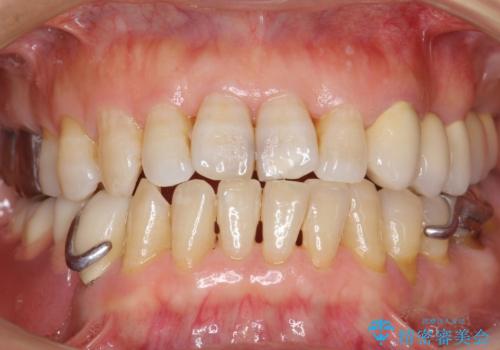

- 左上の歯ぐきが腫れていることを主訴に来院された患者様です。

精査したところ、歯ぐきが腫れている左上の小臼歯(左上4)は保存不可能な状態でした。

インプラント・ブリッジ・入れ歯の選択肢を提案させて頂いたところ、ブリッジをご希望されました。

保存不可能な歯(左上4)を抜去後、ブリッジによる補綴治療を行いました。